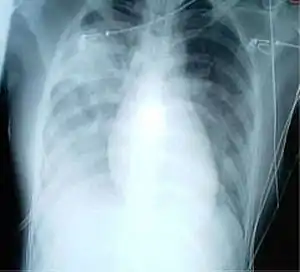

- 14 % étaient sévères (avec dyspnée, fréquence respiratoire supérieure ou égale à 30 par minute, saturation en oxygène sanguin inférieure ou égale à 93 %, pression partielle d'oxygène artériel par rapport au rapport d'oxygène inspiré inférieur à 300 et/ou infiltrats pulmonaires supérieurs à 50 % en 24 à 48 h) ;

Le , en Chine les critères de diagnostic de la maladie changent, ce qui augmente le nombre de cas. En effet, débordés, les hôpitaux du Hubei se basaient sur une radio des poumons, sans analyse de prélèvements ; soigner et isoler plus tôt les malades était prioritaire, et les résultats du test nécessitent 48 heures alors que le diagnostic radiographique est immédiat[184]. De plus, le système de santé chinois ne rembourse les soins qu'aux malades testés positifs. Pour les autres, la facture est de plusieurs milliers voire dizaine de milliers d'euros. Beaucoup hésitaient à se soumettre au test[184].